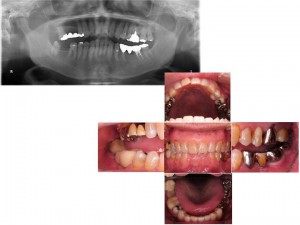

歯を失った部分にインプラントを行うことで、しっかりとした上下の噛み合わせをつくり、さらに部分矯正や適切な被せ物をいれることで、噛み合わせのズレを改善した症例

左下の歯(向かって右下)を失ったことで、咬む相手のなくなった左上の歯が伸びてきてしまったことを気にされて来院された患者さんです。

最終的な被せ物を入れた状態です。

伸びてしまっていた歯の位置関係を改善することで、スムーズな咀嚼を可能とし、また、ブリッジ部分をインプラントに変えたことで長期的にも安定したかみ合わせを作ることが出来ました。

また、かぶせ物に白い材料を選ぶことで、審美的にも良好な結果を得ることが出来ました。